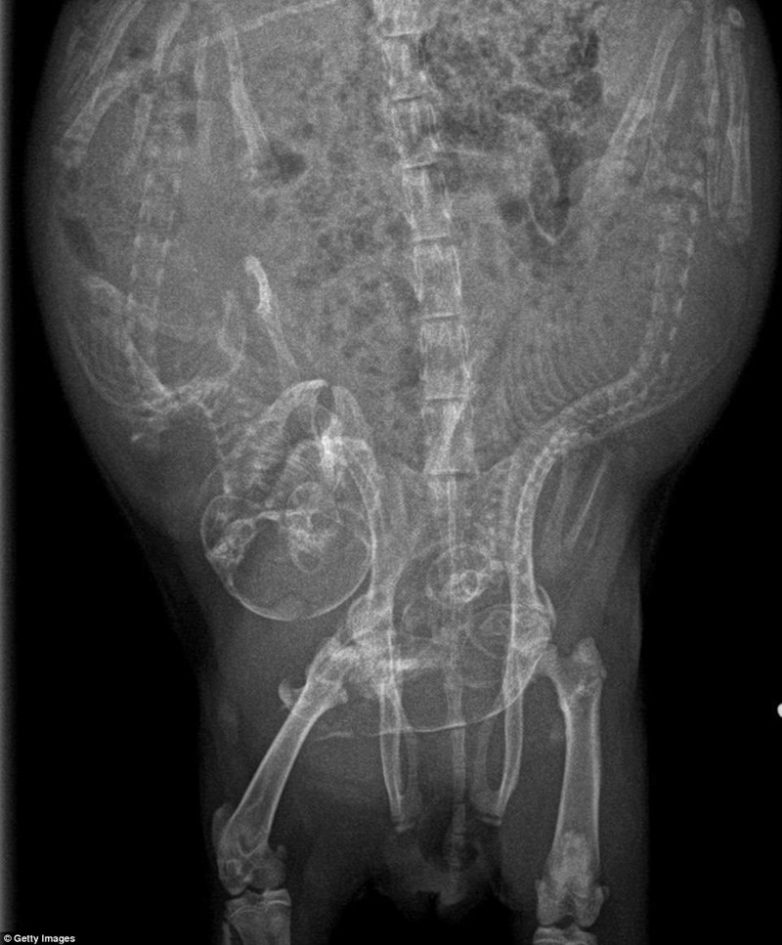

Беременность животных на рентген-снимках

Представляем вашему вниманию серию интересных рентгеновских снимков, на которых можно рассмотреть, как располагаются будущие детеныши енота, летучей мыши или, скажем, бородатой ящерицы в животах их мам.

Для некоторых животных вынашивание сразу нескольких детенышей — это норма, а некоторые (например, летучие мыши, мартышки или олени) рожают только одного (летучие мыши могут выносить до трех детенышей, но это редкость). Что касается длительности вынашивания, то самая короткая беременность — у опоссумов (12-13 дней), а самая длительная — у слонов (20-22 месяца).

Морская свинка